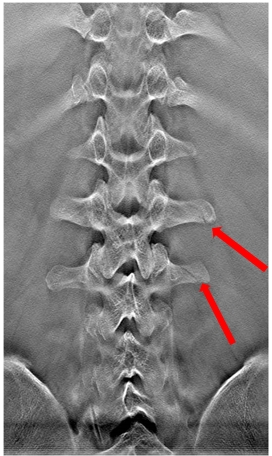

病例四:男,35岁。摔伤入院。

断层融合能够清晰显示腰椎横突骨折。